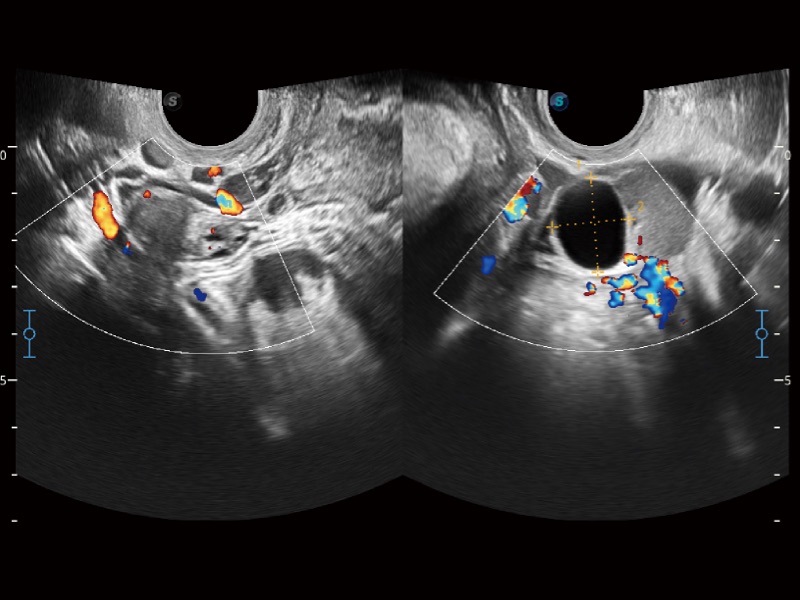

高分辨率血流成像技術(shù)提高了對低速血流信號(hào)的檢測能力。在提高空間分辨率的同時(shí),也克服了血流外溢現(xiàn)象,為用戶提供更加真實(shí)的血流動(dòng)力學(xué)信息。

婦產(chǎn)科應(yīng)用